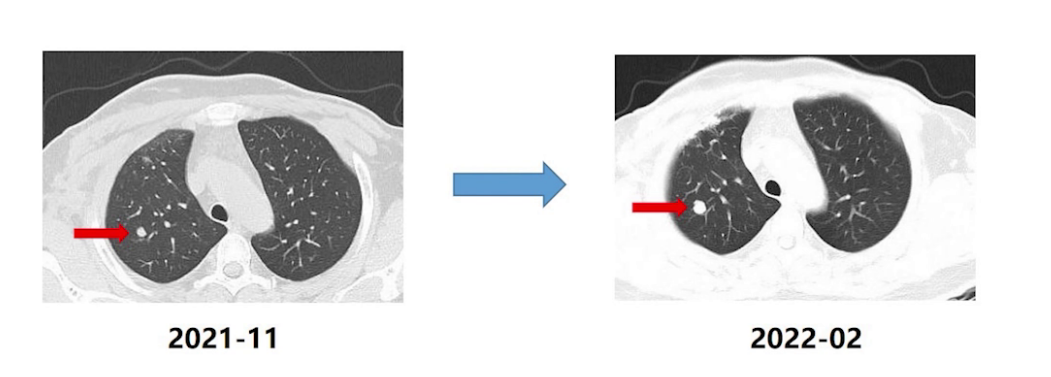

2022年2月16日复查CT提示右肺结节较前增大,疗效评估PD。

基于上述临床研究数据,该患者于2022年2月26日开始维迪西妥单抗治疗8周期,肺转移灶较前明显缩小,疗效评估PR,但出现严重四肢疼痛麻木等周围神经病变,因此暂停使用。